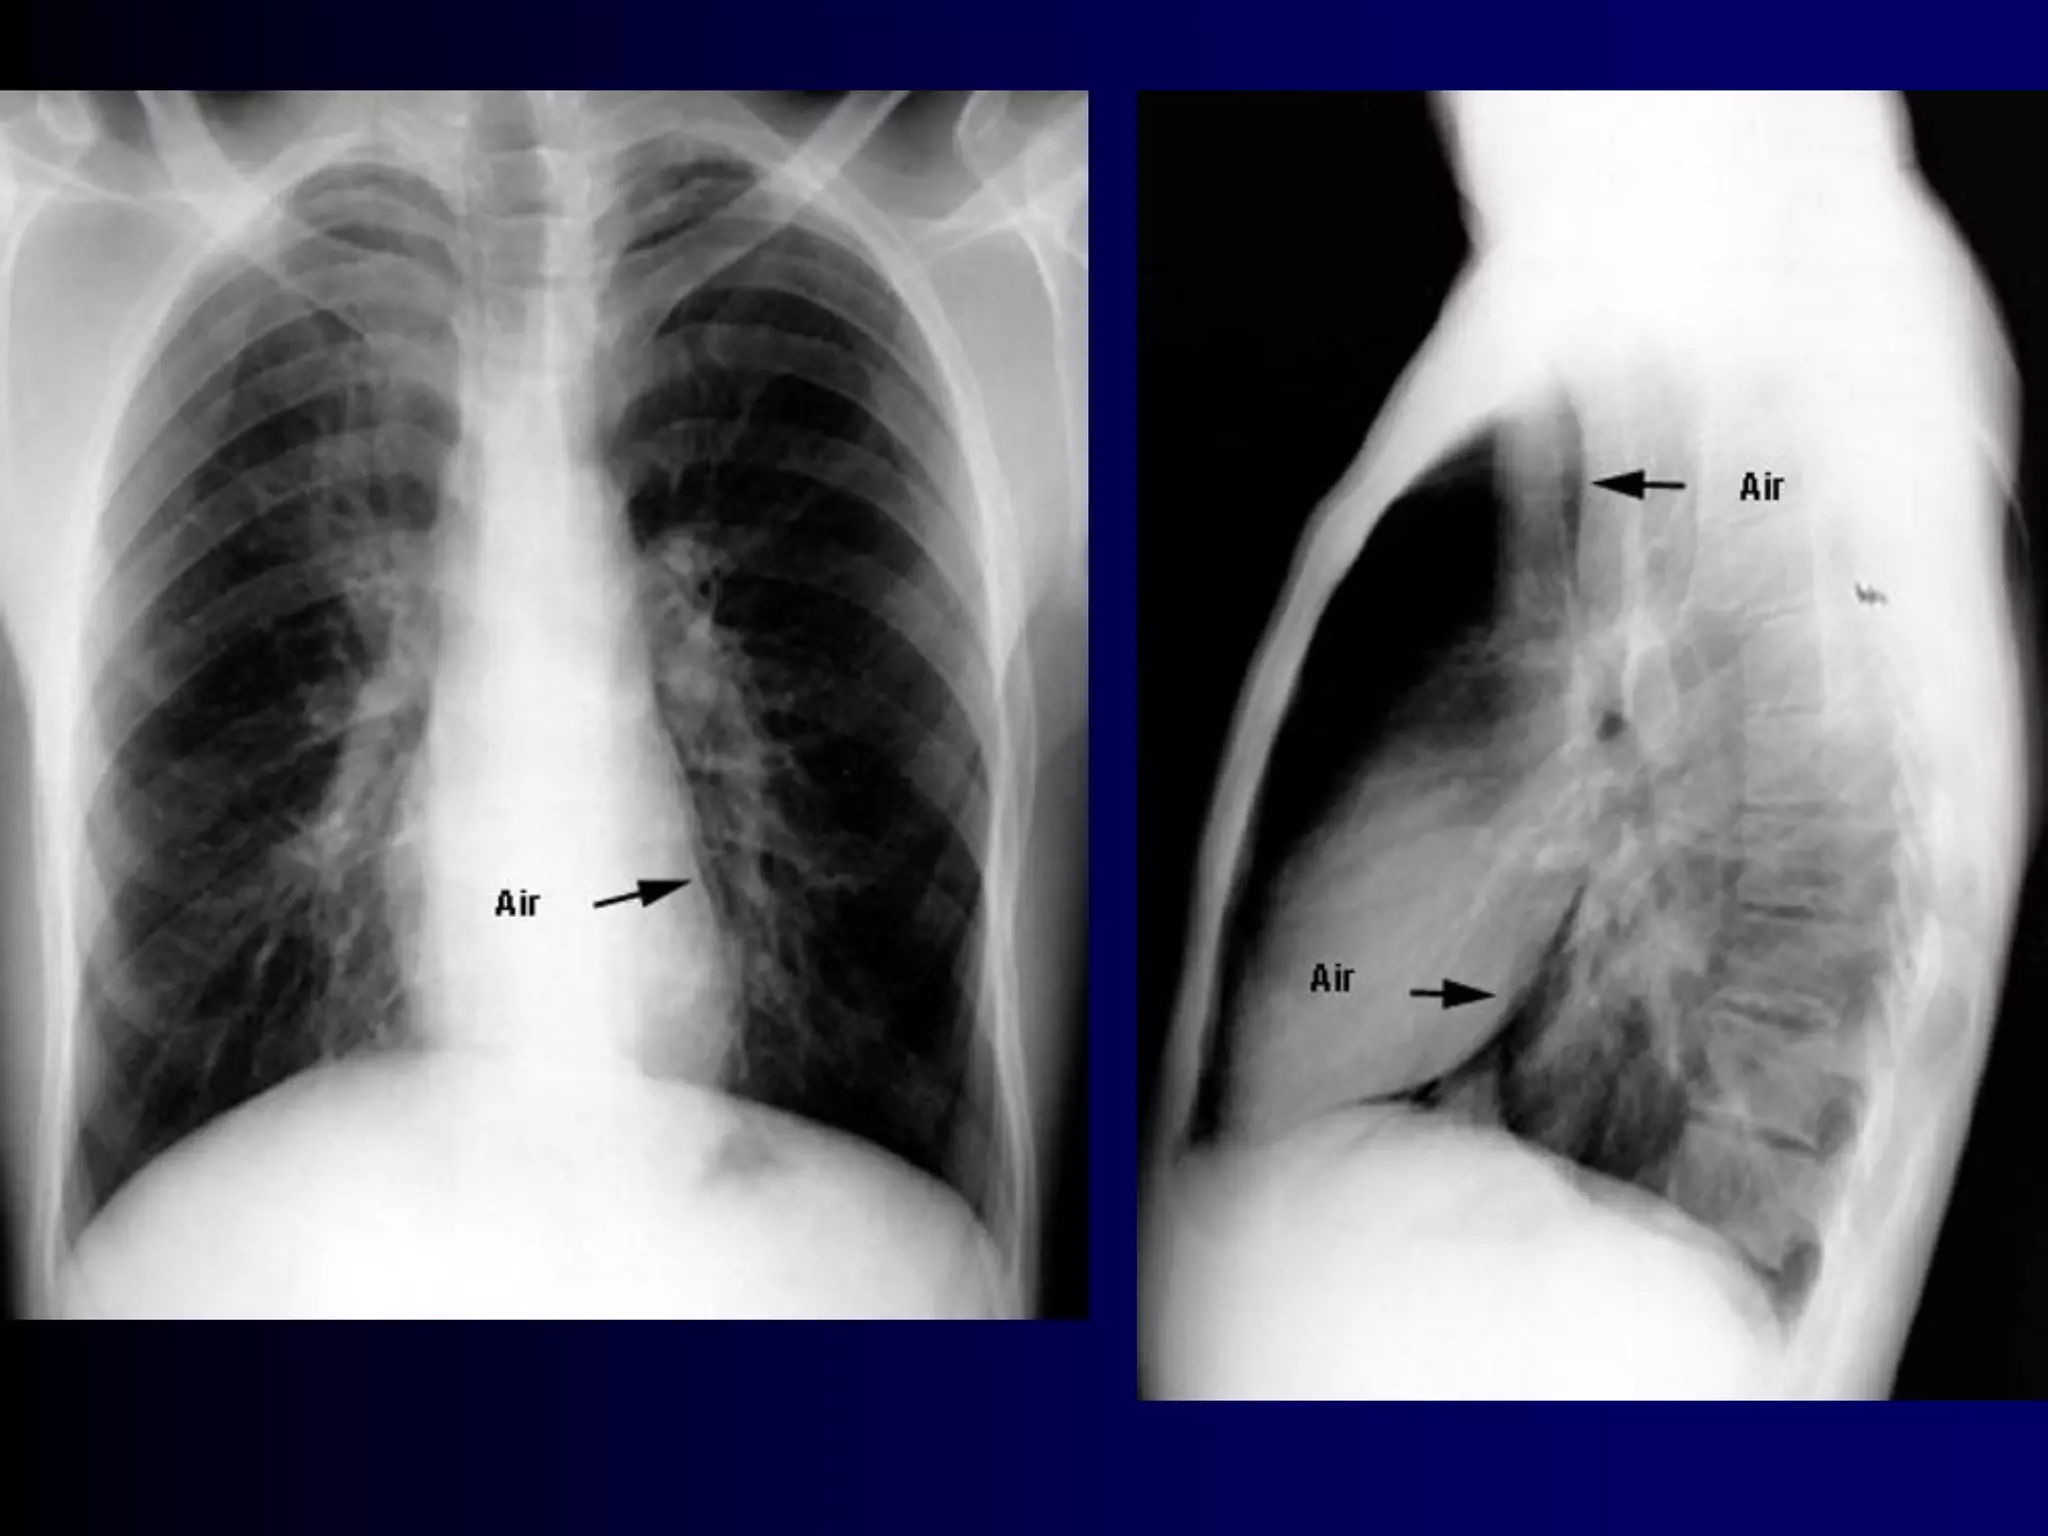

Allergic bronchopulmonary aspergillosis (ABPA) is an

ongoing hypersensitivity reaction in response to

bronchial colonization by Aspergillus, and is a common

cause of poorly controlled asthma. Cystic fibrosis

patients are also often affected. Bronchial obstruction

by mucus and chronic inflammation can lead to

bronchiectasis and lung fibrosis with irreversible loss

of lung function.

Clinical features: Cough productive of sputum, frequent

"bronchitis"; often with dyspnea and wheezing.

Diagnosis:

By constellation of symptoms and objective

findings. "Classic" ABPA would include the

following:

Asthma history

Immediate reactivity on skin prick with Aspergillus

antigens

Precipitating serum antibodies to A. fumigatus

Serum total IgE concentration >1,000 ng/mL

Peripheral blood eosinophilia >500/mm3

Lung opacities on chest x-ray or chest HRCT

Central bronchiectasis present on chest CT

Elevated specific serum IgE and IgG to A.

fumigatus

A skin test is the best first test, as it

is considered 100% sensitive (i.e., a

negative test rules out the condition).

A serum IgE < 1,000 or negative

precipitating antibodies also rule out

ABPA with high confidence.